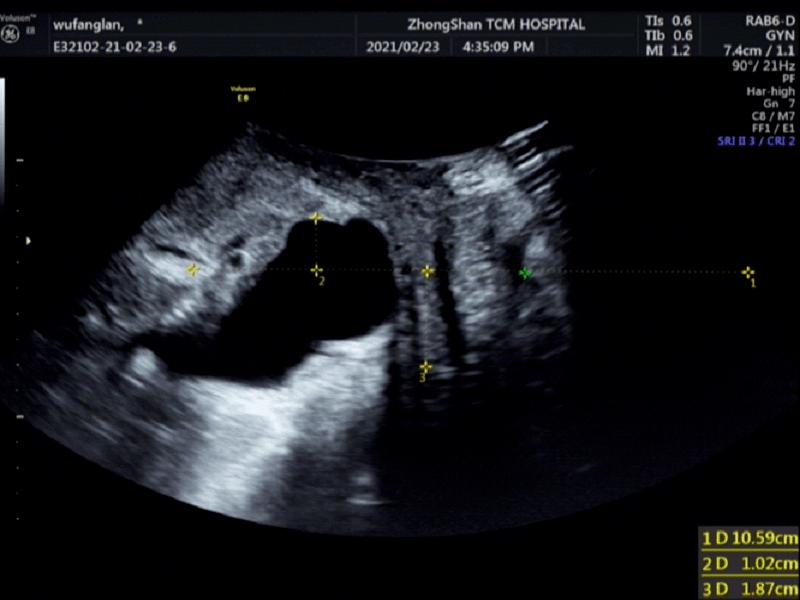

2、影像学检查:以超声为主,既能显示静息状态下女性尿道、阴道、膀胱、膀胱颈、直肠等与耻骨联合下缘的关系,膀胱尿道的角度,又能在Valsalva动作和盆底肌肉收缩时动态观察上述结构的变化,了解膀胱颈活动度等情况。MRI和CT因为价格昂贵或者对人具有放射性而不常应用于诊断膀胱膨出。